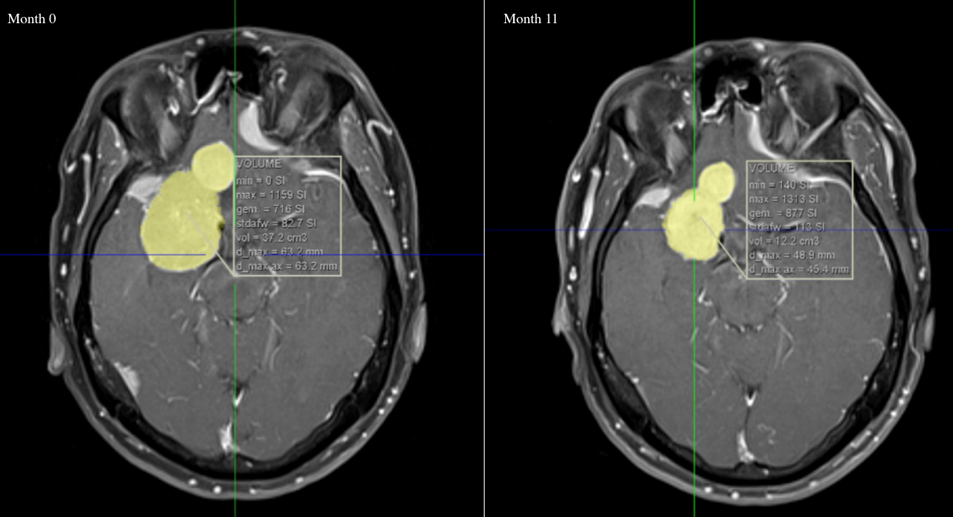

CPA was discontinued as regression of meningiomas after discontinuation of CPA has been described. On follow-up imaging 11 months after cessation of CPA, a regression with 25 cc of the volume of the largest meningioma was recorded (Figure 3 [Fig. 3]).

Figure 3: Large lobulated meningioma in the right anterior fossa. The total volume was 37.2 cm3 at presentation. Eleven months after discontinuation of CPA total volume was reduced to 12.2 cm3.